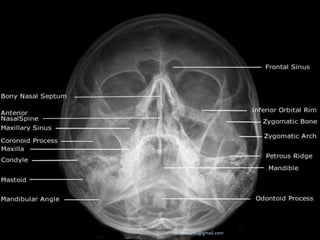

STRUCTURES SEEN

1. FRONTAL SINUSES (SEEN BEST)

2. ETHMOID SINUSES

3. MAXILLARY SINUSES

4. FRONTAL PROCESSOF ZYGOMA AND

ZYGOMATIC PROCESSOF FRONTAL BONE

5. SUPERIOR MARGIN OF ORBIT AND LAMINA

PAPYRACEA

6. SUPERIOR ORBITAL FISSURE

 WATER’SVIEW

STRUCTURES SEEN 1. FRONTALSINUSES (SEEN BEST) 2. ETHMOID SINUSES 3. MAXILLARY SINUSES 4. FRONTAL PROCESSOF ZYGOMA AND ZYGOMATIC PROCESSOF FRONTAL BONE 5. SUPERIOR MARGIN OF ORBIT AND LAMINA PAPYRACEA 6. SUPERIOR ORBITAL FISSURE